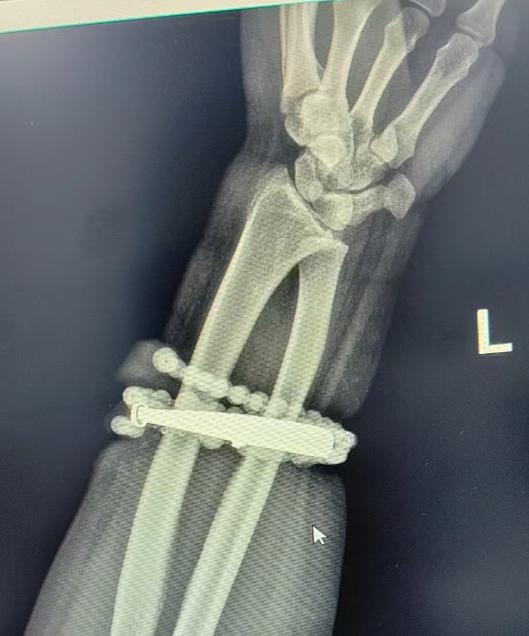

戴了十年沒摘的手鐲、串珠竟長進了肉里,還發炎了!近日,福建省寧德市閩東醫院創傷骨科、手顯微外科就接診了這樣一位患者。

然而,就在兩周前,龔女士的情況急轉直下:手腕不僅疼痛加劇,還出現了明顯的紅腫,甚至有膿液滲出。她這才驚覺——手鐲和串珠,已經有一部分“長”進了肉里,根本取不下來了!

“這是典型的首飾長期壓迫、摩擦,加上細菌感染,引發的慢性炎症和肉芽組織增生。”醫生介紹,此時,手鐲和串珠已經成了一個不斷刺激皮膚、污染傷口的“病灶”,如果不儘快手術取出,感染可能進一步擴散,甚至危及生命或影響手臂功能。

經過一個多小時的手術,醫生們將手鐲和串珠從厚厚的增生組織中完整剝離出來。目前,龔女士恢復良好,已順利出院。